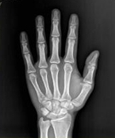

醫(yī)學(xué)影像學(xué)是一門理論性和實(shí)踐性均很強(qiáng)的應(yīng)用科學(xué),包括X線、超聲、MRI、核醫(yī)學(xué)及介入影像學(xué)等。主要用于臨床的各種疾病的診斷和治療,是影像醫(yī)學(xué)生必需掌握的一門課程,是成為一名合格影像醫(yī)生的必備技能。

學(xué)習(xí)醫(yī)學(xué)影像學(xué)是為適應(yīng)醫(yī)學(xué)快速發(fā)展的需要。隨著計(jì)算機(jī)及數(shù)字化技術(shù)的快速發(fā)展,醫(yī)學(xué)影像檢查設(shè)備不斷創(chuàng)新,醫(yī)學(xué)影像學(xué)已經(jīng)成為當(dāng)今醫(yī)學(xué)新興重要學(xué)科。近幾年我國(guó)許多大型醫(yī)學(xué)影像設(shè)備如彩超、螺旋CT、MRI等已配備到縣一級(jí)醫(yī)院,沿海發(fā)達(dá)地區(qū)甚至區(qū)、鎮(zhèn)醫(yī)院亦擁有。如何更好地發(fā)揮這些設(shè)備的社會(huì)和經(jīng)濟(jì)效益,是影像醫(yī)學(xué)生義不容辭的責(zé)任。

學(xué)習(xí)醫(yī)學(xué)影像學(xué)是為了診療疾病有正確的保證。影像學(xué)診斷是對(duì)疾病進(jìn)行較精確定位、定性及定量今斷的學(xué)科,是臨床的常規(guī)檢查,已使過去不能診斷的疾病得到了早期適時(shí)正確的診斷和治療。影像技術(shù)的應(yīng)用在一定程度上決定了醫(yī)療水平的高低,關(guān)系到臨床各科室各種疾病的診斷,臨床醫(yī)學(xué)對(duì)影像診斷的依賴性越來越大。因此,掌握好各種影像檢查方法的適應(yīng)癥以及各種基本病變的表現(xiàn)是正確作出最恰當(dāng)診療的保證。